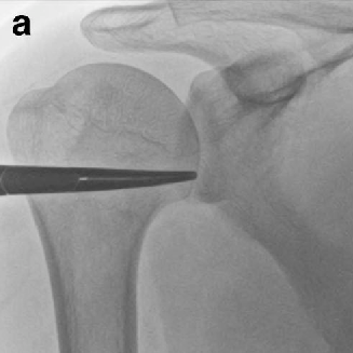

오십견의 치료

관절 가동 범위를 확대하기 위해 관절낭 팽창술과 함께 인대강화주사를 할 수 있으며 이 후 재활기간 동안 어깨관절도수를 시행하게 됩니다. 심각한 오십견의 경우 어깨부위를 마취하고 수동 조작을 통해 어깨 관절 가동범위를 정상화 할 수 있습니다.